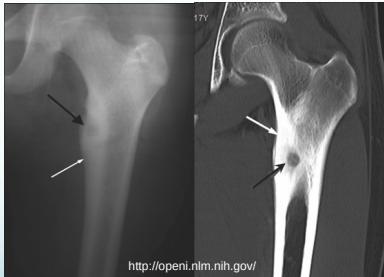

Osteoid Osteoma

- Small tumor (<1 cm)

- Young adults

- Pain, pain, pain:

- Typically relieved by Salicylates

- Sites: Femur, tibia, spine

- X-ray:

- Small radiolucent “nidus”

- Surrounded by sclerotic bone

- CT: Shows “nidus” better

- scan: hot

- Treatment: surgical excision, or thermal ablation

Source: Orthopedic Radiology. A Greenspan. Lippincott-Raven

Sources: Apley’s System of Orthop. And Fractures, http://openi.nlm.nih.gov/

Clinical Example

- 11 year old boy: Pain in left hip